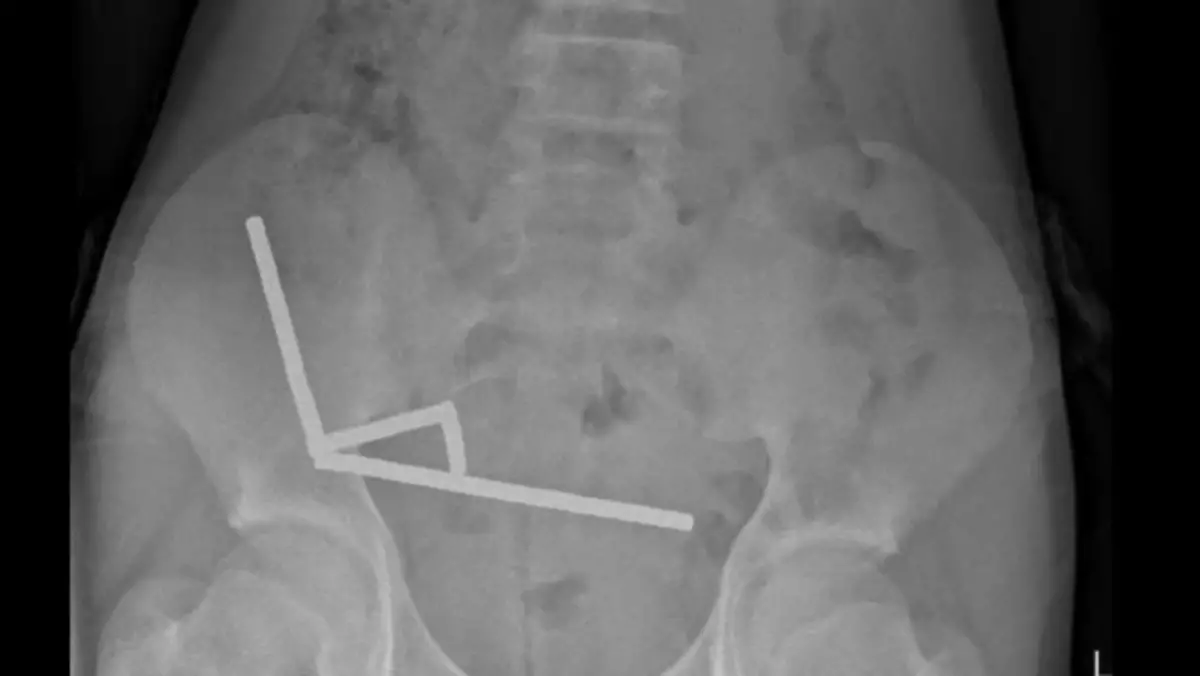

A 13-year-old boy had to have part of his bowel removed after he swallowed hundreds of magnets. The child, from New Zealand, had ingested over 100 high-power magnets, believed to have been purchased from online shopping site Temu, according to a report in the New Zealand Medical Journal on Friday (October 24). After suffering from abdominal pain for four days, the teenager was admitted to Tauranga Hospital, where he told doctors that he had swallowed the magnets about a week earlier. Imaging scans revealed four chains of tiny magnets, which were all 'in separate parts of bowel' but 'adhered together due to magnetic forces'. The presence of the magnets within the bowel caused a health condition called 'pressure necrosis', in which tissues die due to prolonged pressure that compresses blood vessels and cuts off the oxygen supply. Emergency surgery was required to remove the magnets as well as various sections of the bowel that were damaged. The boy spent eight days in hospital recovering from the ordeal, with the report explaining: "Ingestion of multiple magnets can have serious consequences, including pressure necrosis, perforation, obstruction, fistula and sepsis. "Given the majority are managed with surgical intervention, this can lead to further complications later in life, including adhesional bowel obstruction, abdominal hernia and chronic pain. "Preventative strategies are important to reduce risk of harm to paediatric patients." Both Australia and New Zealand banned small, high-powered magnets back in 2013 due to the dangers of swallowing them. However, it can be difficult to regulate their sale online, as the report said: "Accessibility to high-power magnets is a rising concern for our paediatric population, which may be due to the ability to purchase from online marketplaces at inexpensive prices." A UK study found that 68 per cent of patients who had swallowed a magnet were asymptomatic, while the rest mainly experienced abdominal pain and vomiting. In a statement to The New York Post, a Temu spokesperson said: “We are sorry to learn about the reported incident and wish the boy a full and speedy recovery. “At this stage, we have not been able to confirm whether the magnets involved were purchased through Temu or identify the specific product listing. “Our teams are reviewing relevant listings to ensure full compliance with local safety requirements. “Any products found to be non-compliant will be removed, and we will take firm action against any sellers found to have breached our platform rules or local regulations.” LADbible Group has also reached out to Temu for further comment.